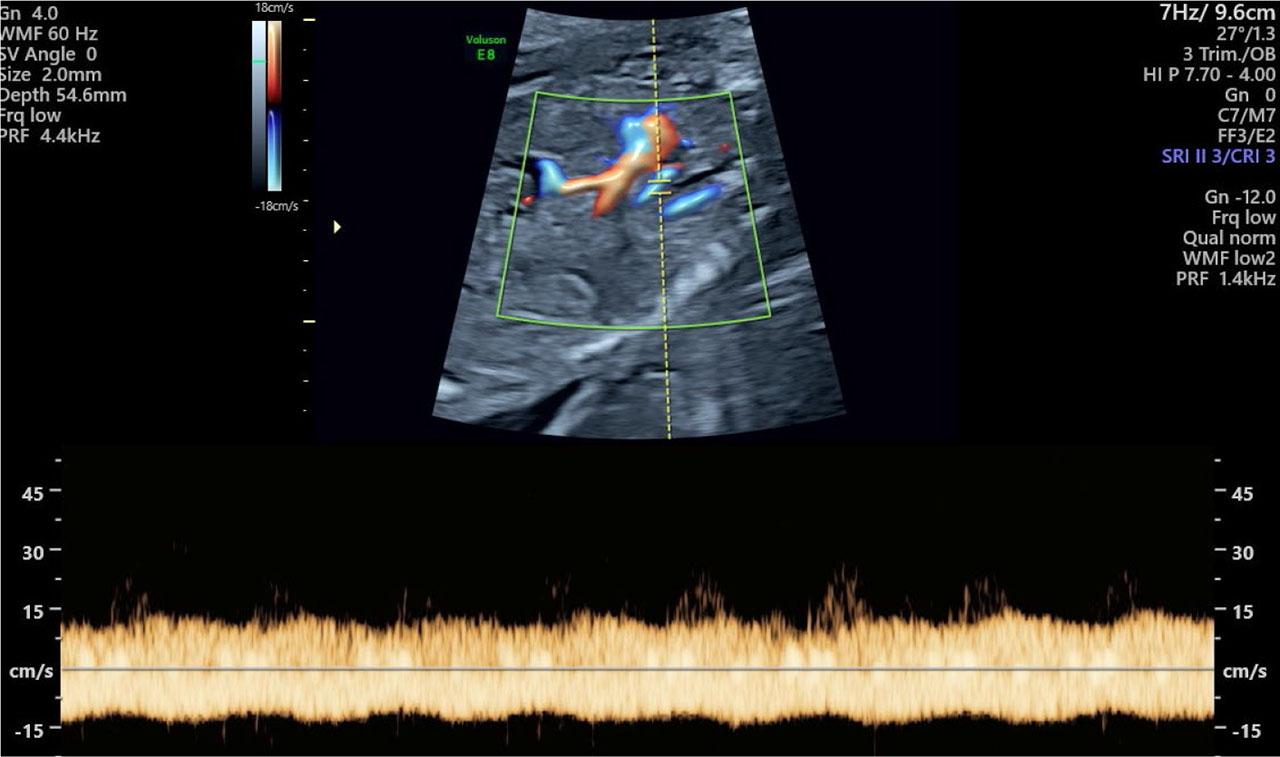

Fig. 4.